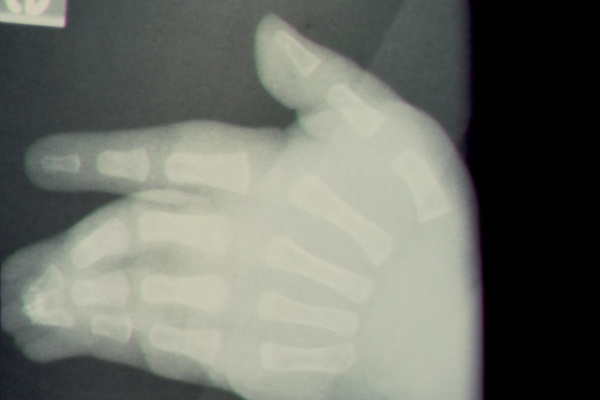

Clinical Example: Syndactyly

syndactyly